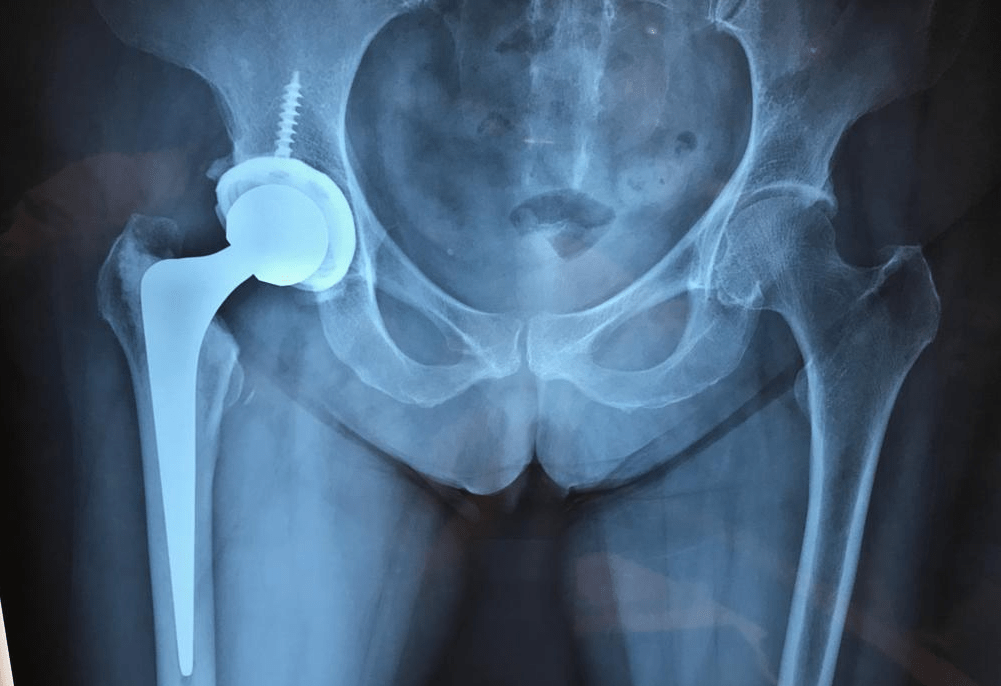

Foto de Prótese de Quadril

A prótese de quadril é uma alternativa segura e eficiente para quem enfrenta dores intensas e limitações de movimento. Esse procedimento é indicado para pacientes com condições como artrose avançada, fraturas ou desgaste da cartilagem, devolvendo qualidade de vida e liberdade de movimentos.

Na cirurgia de prótese de quadril, as partes danificadas da articulação são substituídas por componentes, feitos para imitar a função e o movimento do quadril natural. Com essa substituição, o paciente experimenta alívio imediato da dor e melhora na capacidade de realizar atividades do dia a dia.

A cirurgia consiste na remoção da cabeça do fêmur e do acetábulo deteriorados, com substituição por componentes artificiais feitos de metal, cerâmica e polietileno. Pode ser feita por via posterior, lateral ou anterior, conforme o caso.